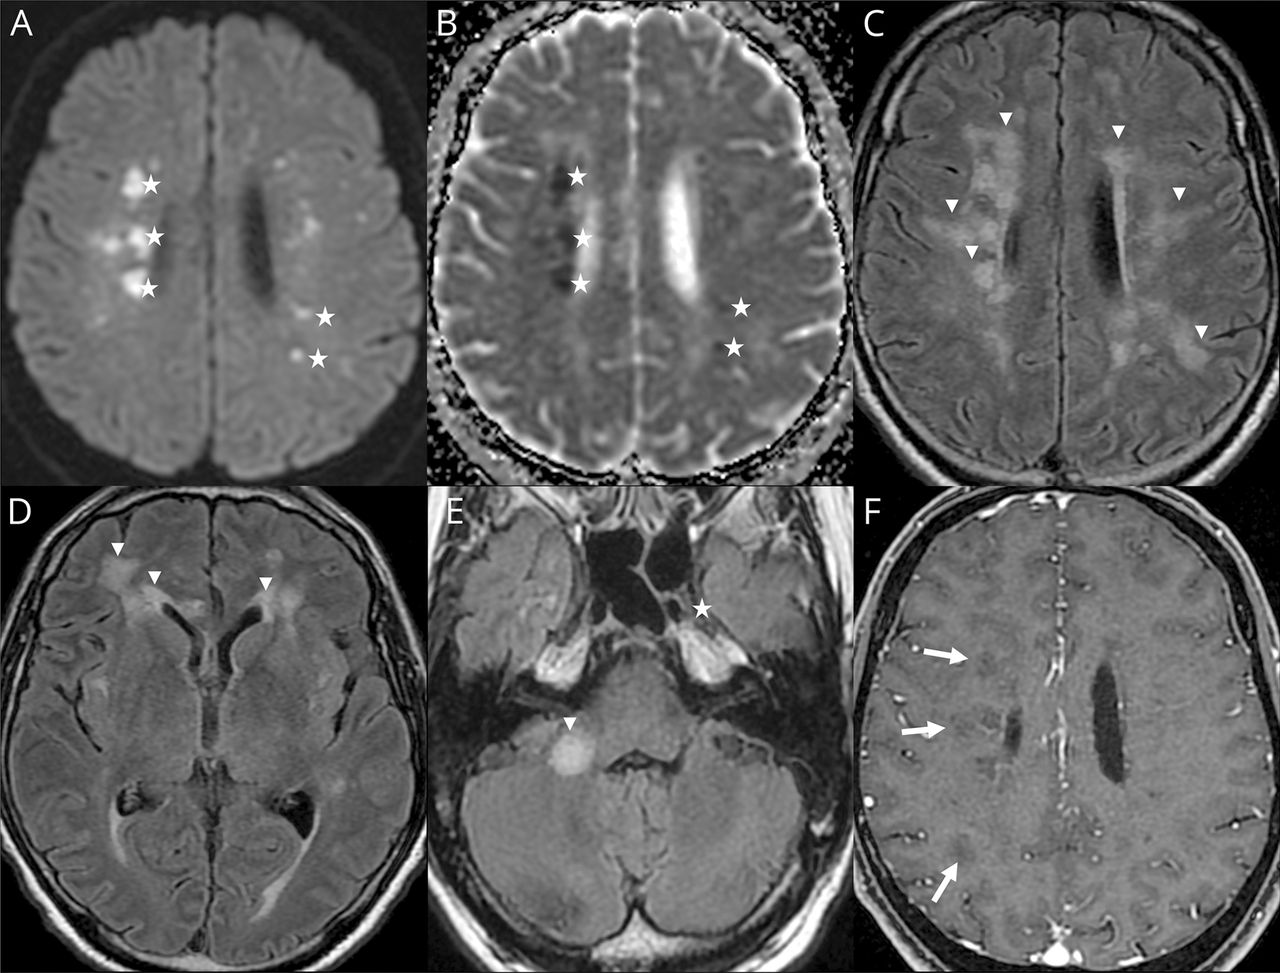

Ischemic strokes (27%) (figure e-1, available from Dryad,doi.org/10.5061/dryad.w9ghx3fm7), LME (17%) (figure 1), and encephalitis (13%) (figures 2and3and figure e-2, available from Dryad) were the most frequent neuroimaging findings. LME was seen on both postcontrast T1-weighted and FLAIR sequences and was even better visualized when delayed postcontrast FLAIR was performed. These signal abnormalities were not present on precontrast T1 or FLAIR images.

(A, E, I) Axial fluid-attenuated inversion recovery (FLAIR), (B, F, J) axial diffusion, (B, F, J) apparent diffusion coefficient (ADC) map, and (D, H, L) postcontrast T1-weighted MRIs. Man 60 years of age: subcortical, periventricular, corpus callosum, and posterior fossa white matter FLAIR hyperintensities without contrast enhancement (arrows). Some lesions appear hyperintense on diffusion-weighted MRIs, with decreased ADC corresponding to cytotoxic edema (stars). Other lesions present an ADC increase corresponding to vasogenic edema (cross).

Among the 8 encephalitis, 2 cases of limbic encephalitis, 2 cases of radiologic acute hemorrhagic necrotizing encephalopathy, 2 cases of miscellaneous encephalitis, 1 case of radiologic ADEM, and 1 case of CLOCC were described.